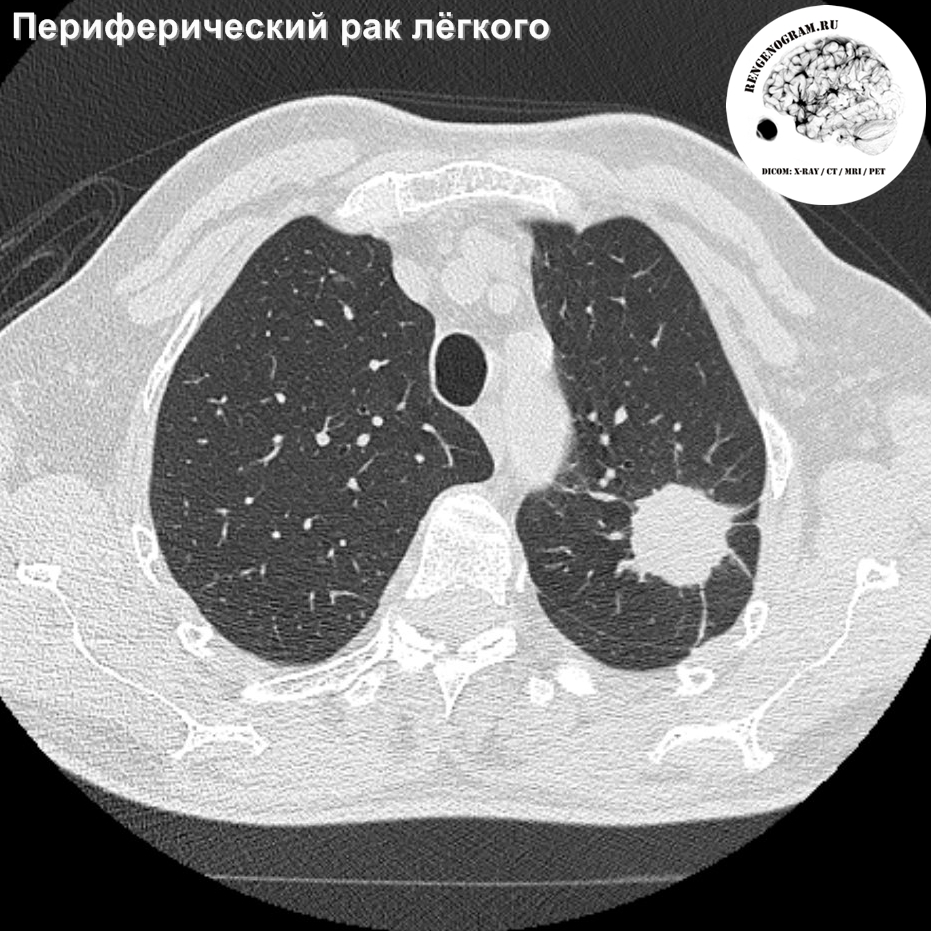

Рентгеновские снимки опухоли Панкоста